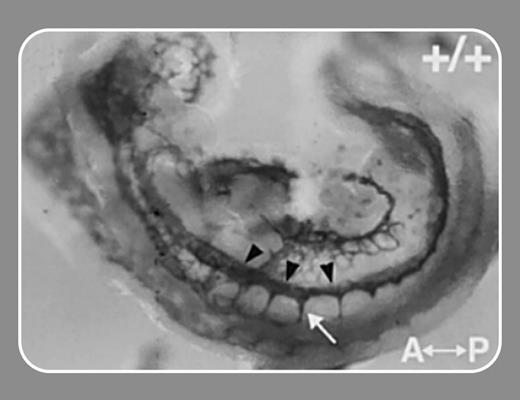

In this issue, Kearney and colleagues (page 4527) use Vegfr-1 null mice and the elegant technique of confocal time-lapse imaging to examine the dynamics of vascular sprout formation in order to test a role for VEGFR-1 in VEGF-induced endothelial cell migration. Their experiments reported here do indeed show decreased sprouts and reduced migration rate in differentiated Vegfr-1-/- vessels. Perhaps the most surprising finding is the capacity of an sflt-1 transgene to rescue the mutant phenotype. The implication is that sflt-1 can bind local VEGF-A and alter the concentration gradient of this growth factor, which drives both sprouting and endothelial cell migration.

A critical challenge for clarifying the biologic role of different VEGF receptor complexes is to identify the downstream genes influenced by such signaling and to associate these genes with the various steps involved in angiogenesis and vasculogenesis (eg, mitogenesis, chemotaxis, migration, tube formation, and enhancement of vascular permeability). To this end, Zippo and colleagues (page 4536) have used a comparative microarray analysis of Vegfr-2 wild-type (+/+) and -/- embryonic stem (ES) cells to identify downstream transcription targets of VEGFR-2 signaling. The screen has revealed that Pim-1, a gene encoding a serine/threonine kinase, plays a role in the differentiation of ES cells to endothelial cells and smooth muscle cells and may thereby play a role in early vascular development. Furthermore, Pim-1 appears to be required for VEGF-A-dependent proliferation and migration of endothelial cells. Another study recently prepublished in Blood identified a VEGF-A target gene called DSCR1 that regulates the expression of inflammatory markers in endothelial cells.1 FIG2